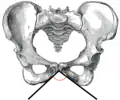

Angle sous-pubien féminin